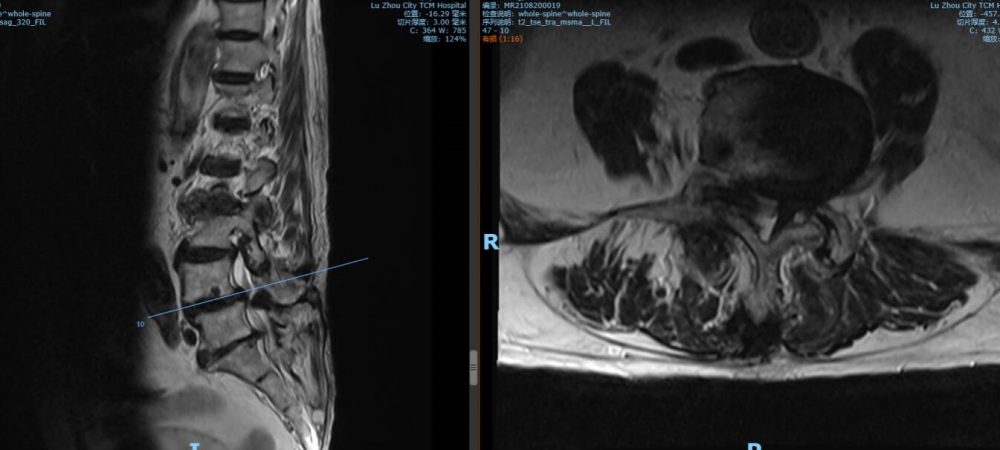

腰4 5椎間盤CT

腰4 5椎間盤MRI

腰5 骶1椎間盤CT

腰5 骶1椎間盤MRI

瀘州市中醫(yī)醫(yī)院骨傷二科主治中醫(yī)師胡建超介紹,李謹行老人患有腰椎管狹窄癥 、腰4椎I°滑脫 、脊柱退行性側(cè)彎畸形 、冠狀動脈粥樣硬化性心臟病、心律失常、高血壓2級等17種疾病,同時處于慢性阻塞性肺病加重期和腦梗塞恢復(fù)期。92歲、全身多種疾病,隨時可能會有突發(fā)情況,要做這樣一個大手術(shù),對醫(yī)生和患者來說,無疑都是一個巨大的挑戰(zhàn)。